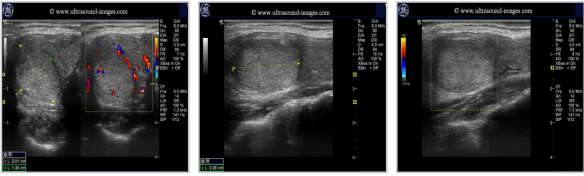

Pics form ultrasound-images.com :

FOLLICULAR ADENOMAthyroid_follicular adenomas